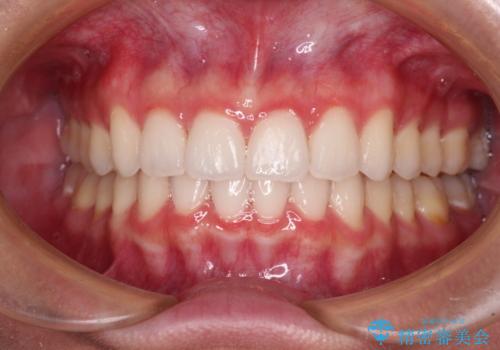

- 前歯2本が飛び出してることを気にして来院された患者様です。

全体的に黄ばんだ歯の色も気になるとのことで、マウスピース矯正により飛び出した前歯を治しつつ、ホームホワイトニングを併用して黄ばみを解消していくこととしました。

歯と歯の間を削ることで、飛び出した前歯が引っ込み、スッキリとした口元となりました。

歯の黄ばみも改善され、明るい歯並びとなりました。